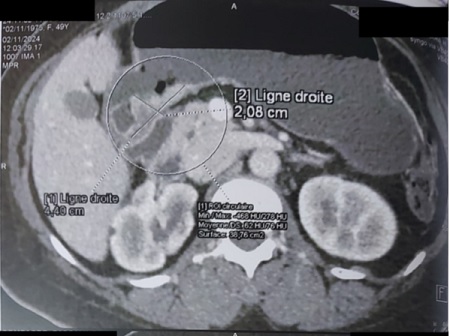

Histopathological examination of the biopsies concluded to a poorly differentiated adenocarcinoma of the lesser curvature. Thoraco-abdominopelvic CT scan revealed posterior gastric wall thickening measuring 44 mm in height and 24 mm in thickness, without metastatic lesions (Image 2).

Abdominal CT scan image showing a thickening of the posterior wall of the stomach Picture 2 : Abdominal CT scan image showing a thickening of the posterior wall of the stomach measuring 44 x 24 mm